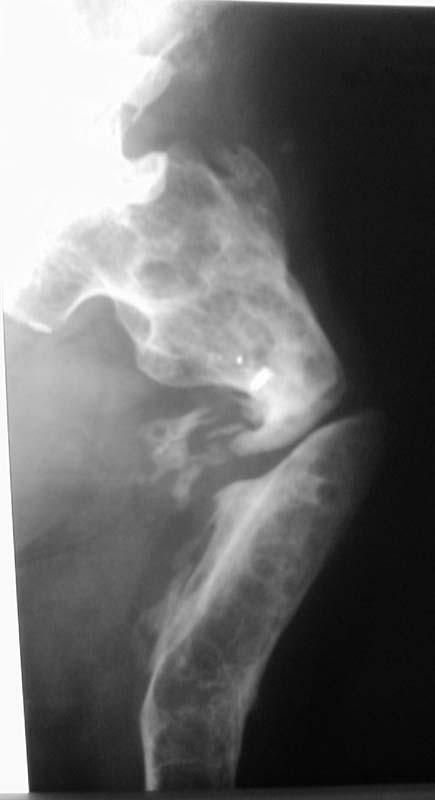

Коллеги! Прошу оказать консультативную помощь! Мужчина, 42 года.В 1994 году - перелом бедра, операция - накостный остеосинтез пластиной.

Осложнение - остеомиелит. Удаление пластины, резекция кости на протяжении 15 см, неудачная попытка замещения дефекта по Илизарову. Сращения не было. В течение 6 лет свищей нет. Укорочение - 13 см. Соматически без особенностей.Лечение? Заранее благодарю! С уважением,А.В.ВладзимирскийДонецкий НИИ травматологии и ортопедииДонецк, Украина

Судя по представленному снимку, есть 3 деформации – Варусная в области ложного сустава - 70°, Вальгусная - 35° в средней трети бедра, и ещё одна вальгусная 8° в области дистального метаэпифиза бедренной кости. Если бы пациент попал ко мне, я сделал бы трилокальный остеосинтез – Открытый погружной копрессионный в области ложного сустава, остеотоми на вершине деформации средней трети бедра для удлинения и коррекции деформации и коррегирующую остеотомию через верхний край мыщелков бедренной кости. Для оппонентов такой тактики сразу оговорюсь, что коррекция анатомической и механической оси при наличии срастающегося ложного сустава критична для профилактики рефрактуры.